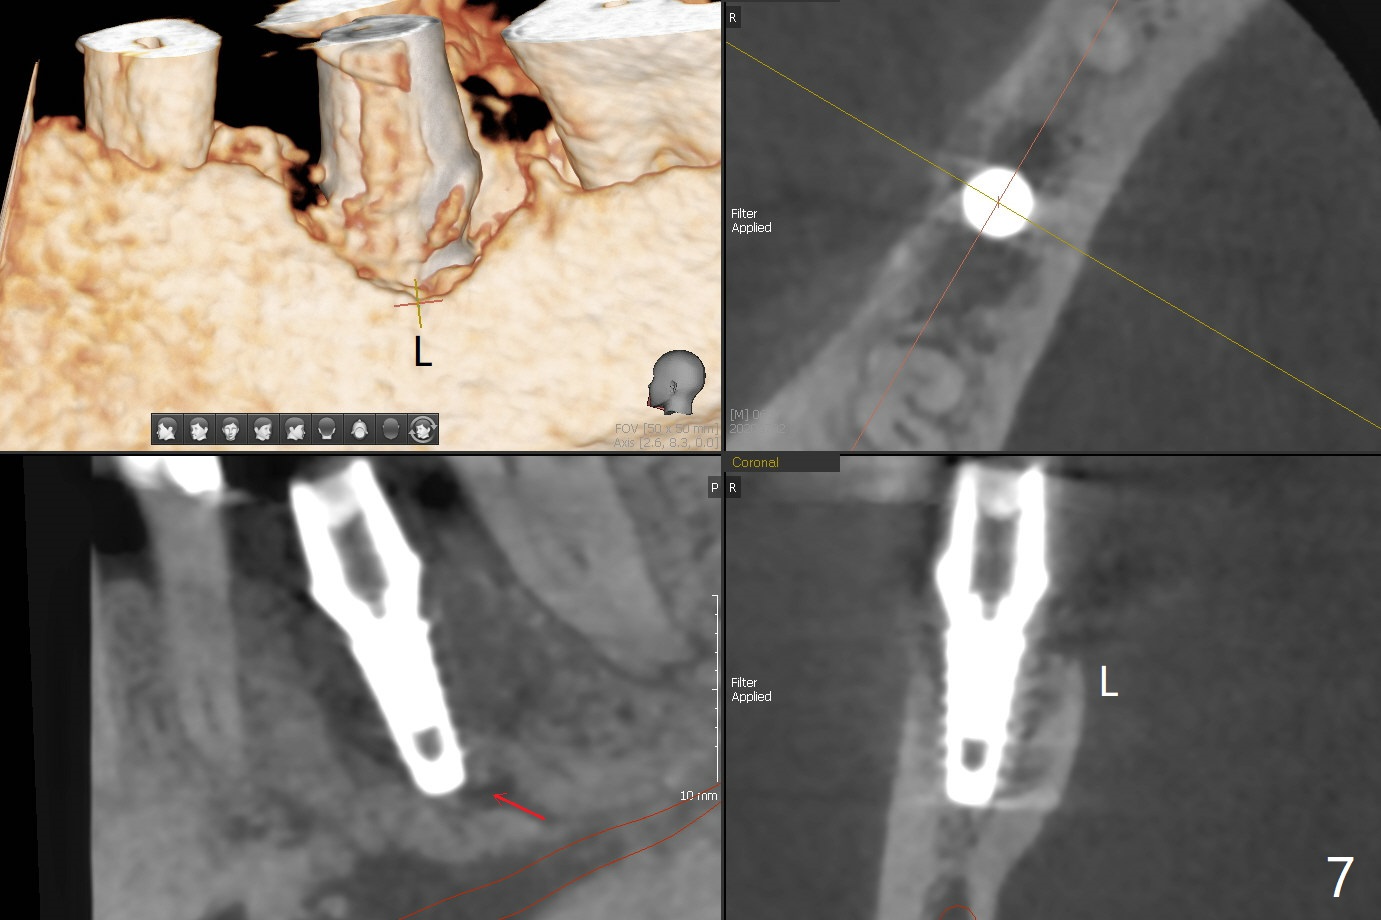

As planned, the crown of the tooth #30 with lingual (Fig.1 L) caries is removed and flattened with surgical handpiece so that the guide is able to be seated without interference. The osteotomy by 10.5 mm offset bone trimmer is lingual (Fig.2 white circle; due to in part the lingual caries and in part design error); in order to let the osteotomy to bounce back buccal, the part of the buccal roots are removed by surgical bur (arrows). The initial osteotomy by 2.2 mm drill is in the middle of the septum (Fig.3). After the last drill (3.5x11.5), the remaining roots are easily removed with proximators; a 4x11 mm dummy implant is placed with low stability and supracrestal lingual (Fig.4). Therefore a 4.5x9 mm final implant is placed with low torque. Following 4x11.5 mm drill, the torque increases to 20 Ncm. With insertion of healing screw, sticky bone (Fig.4 *: .5-1 mm cortical/cancellous allograft) is heavily packed around the implant (arrow), which apparently allows removal of the healing screw and placement of a 6x5.7(3) mm pair abutment without loosening the underlying implant. More bone graft is placed (Fig.6), followed by 2 pieces of PRF membranes. Although the implant is slightly buccally placed (Fig.7, due to over-removal of the buccal root, Fig.2 arrows), it is placed in the septum (Fig.8 S). To further compensate for the low implant stability, setting acrylic is applied in the edentulous area, particularly into the undercuts of the neighboring teeth (Fig.9 *) and around the abutment. The lingual margin of the acrylic dressing is extended (Fig.10 arrow) to cover the soft tissue defect associated with the lingual caries. As compared to the design (4x10 mm, Fig.11), the implant (4.5x9 mm, Fig.12) is placed buccal and ~ 2 mm deeper, reducing the chance of periimplantitis. The acrylic dressing is in place, but has mobility. The gingiva is healthy 2 weeks postop. The dressing is removed 1 month postop; the socket heals around the abutment buccal (Fig.13) and lingual (Fig.14). In spite of the immediate provisional, the abutment margin is substantially subgingival mesial 4 months postop, extremely difficult to take impression. A smaller diameter and longer cuff abutment is placed (Fig.15). The lingual gingiva heals normal 5 months postop, immediately before cementation (Fig.16).